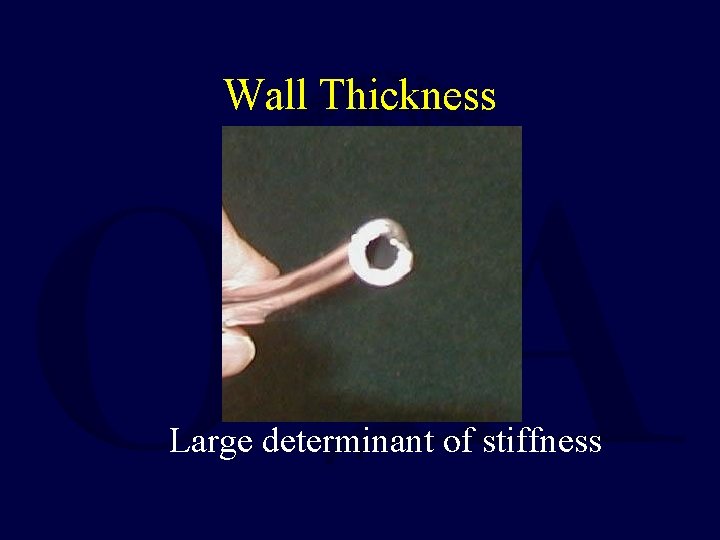

Wall Thickness Large determinant of stiffness